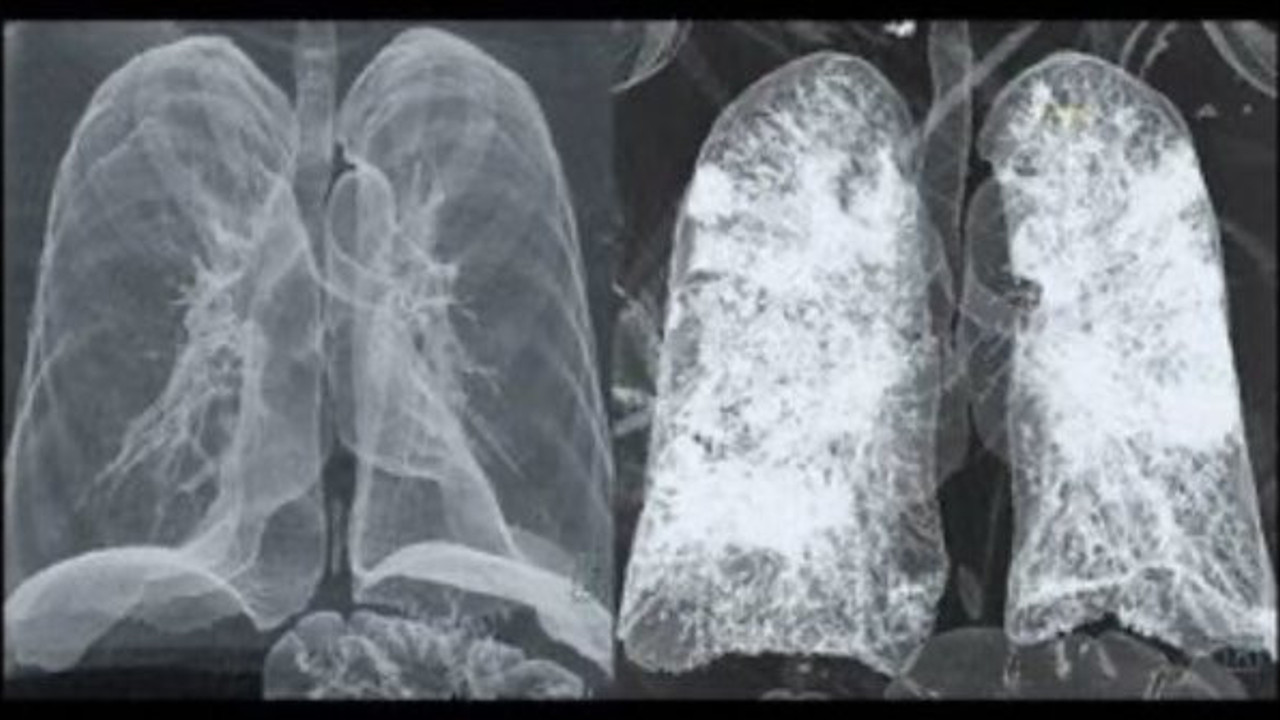

Radyoloji uzmanı Prof Dr Güner Sönmez, Twitter’dan yaptığı paylaşımda bir korona virüs hastasının tomografi görüntülerini paylaştı.

Paylaşımına "korona virüsün öncesi ve sonrası" notunu düşen Sönmez, takipçilerinin de sorularını cevaplandırdı.

Prof. Sönmez, sigara içen hastalarda durumunda daha ağır yaşanacağını belirtirken, "Tabii ki, sigara içenlerde daha ağır hasar oluşuyor" ifadelerini kullanıyor.

Bir takipçisinin "Bu hasta kurtulabilir mi?" sorusuna da cevap veren Prof. Hastanın kurtulabileceğinin altını çiziyor. Akciğerdeki tahribatın kalıcı olup olmadığına da yanıt veren Sönmez, "Çok az bir hastada fibrotik bant dediğimiz bağ dokusu oluşuyor. Uzun dönem sonuçları bilmiyoruz henüz" diyor.

Öte yandan Güner Sönmez, her Covid-19 hastasının salgını bu derece ağır yaşamadığını belirtiyor.